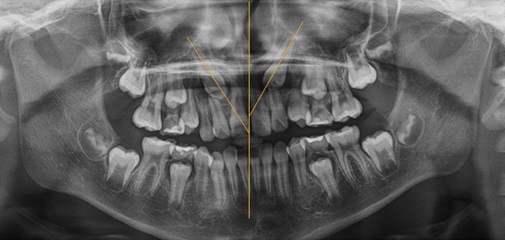

문제 1: Leuven University conducted a study regarding pre-surgical treatment planning of maxillary canine impactions using panoramic vs cone beam CT imaging.

(1) Evaluators were able to better evaluate canine position, contact with the lateral incisors, and incisor root resorption when using CBCT image.

(2) Evaluators had (higher, lower) confidence in their treatment plan when using CBCT image.

(3) (More, Fewer) treatment plans were made to extract the impacted canine when using CBCT image.

답: (2) higher, (3) Fewer